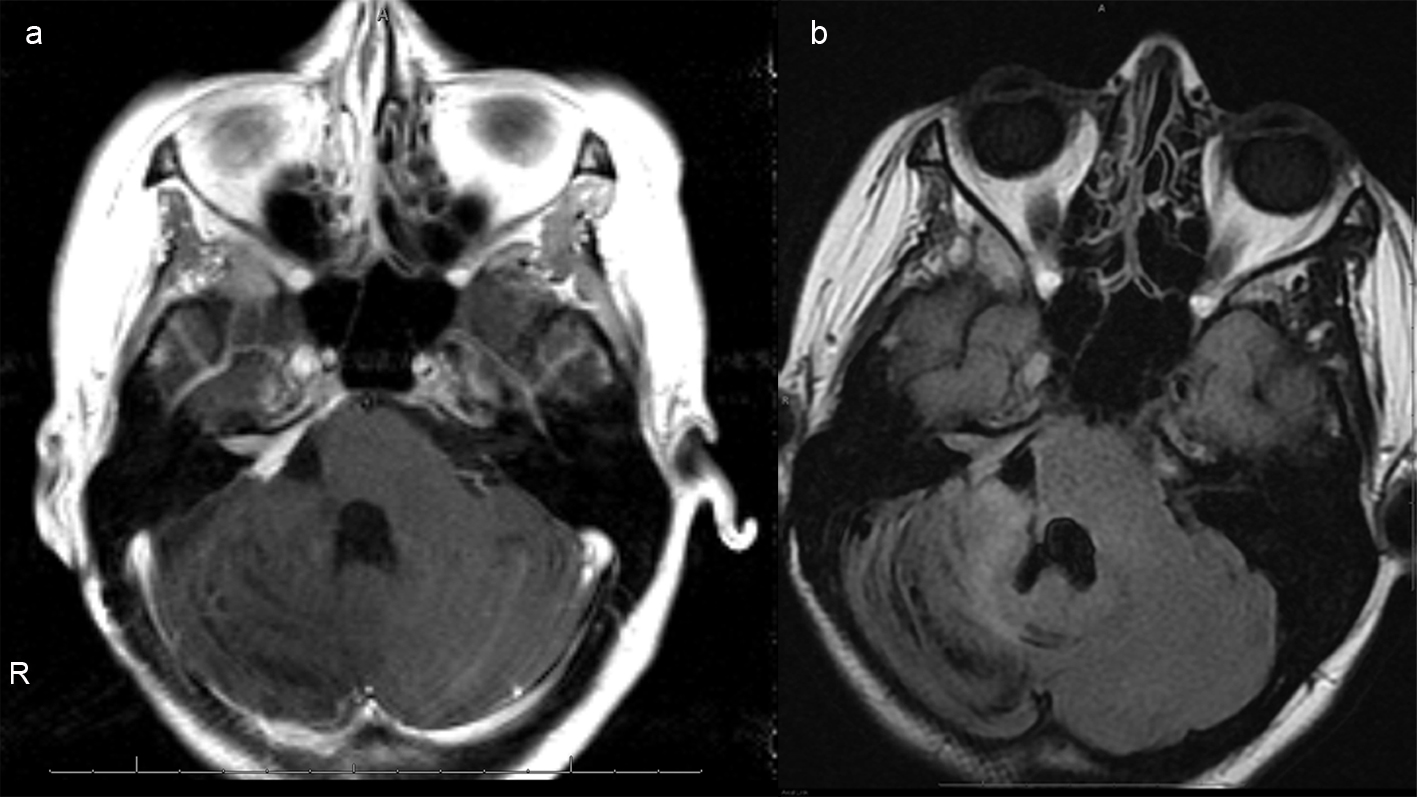

A 26 years old 30-week pregnant female initially presented for neurosurgical evaluation of an incidentally discovered right cerebellopontine (CP) angle mass. She underwent a head CT as part of routine trauma evaluation after a motor vehicle accident (Fig. 1). During her emergency room evaluation, she admitted to progressive decreased hearing in right ear with intermittent tinnitus the past several months. She also described occasional pain behind the right eye and pain along right side of the face. A non-contrast MRI confirmed a large right CP angle mass consistent with meningioma (Fig. 2a, b, c).

![]() Click for large image | Figure 2. (a), Axial T2 image of the posterior fossa confirms the presence of a large extra-axial T2 hyperintense mass. There is mass effect on the adjacent pons and right cerebellar hemisphere. Foci of hemorrhage are present within the medial aspect of the mass. (b), Axial FLAIR image shows no surrounding edema. Focal abnormal T2/FLAIR signal is seen within the internal auditory canal of unclear significance. Abnormal signal with the same characteristics as the dominant mass extends within the right Meckel's cave. (c), Axial DWI image demonstrates mild, diffuse restricted diffusion is noted. The ADC map is not shown, however confirms the DWI findings. |